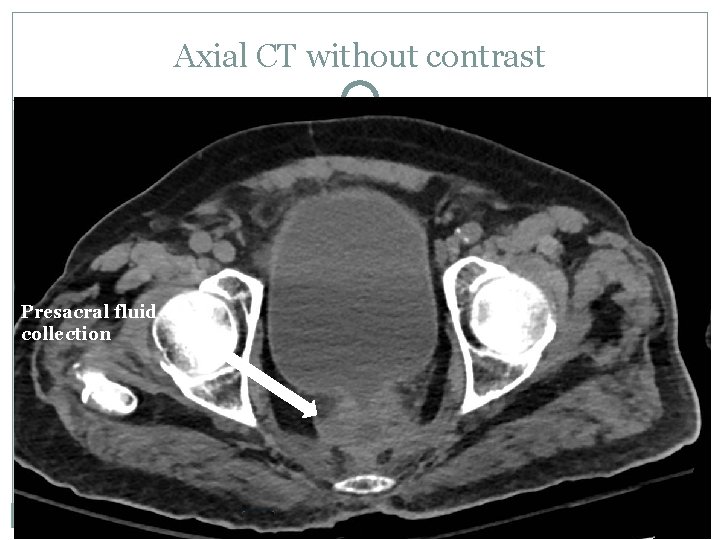

Axial CT without contrast Presacral fluid collection